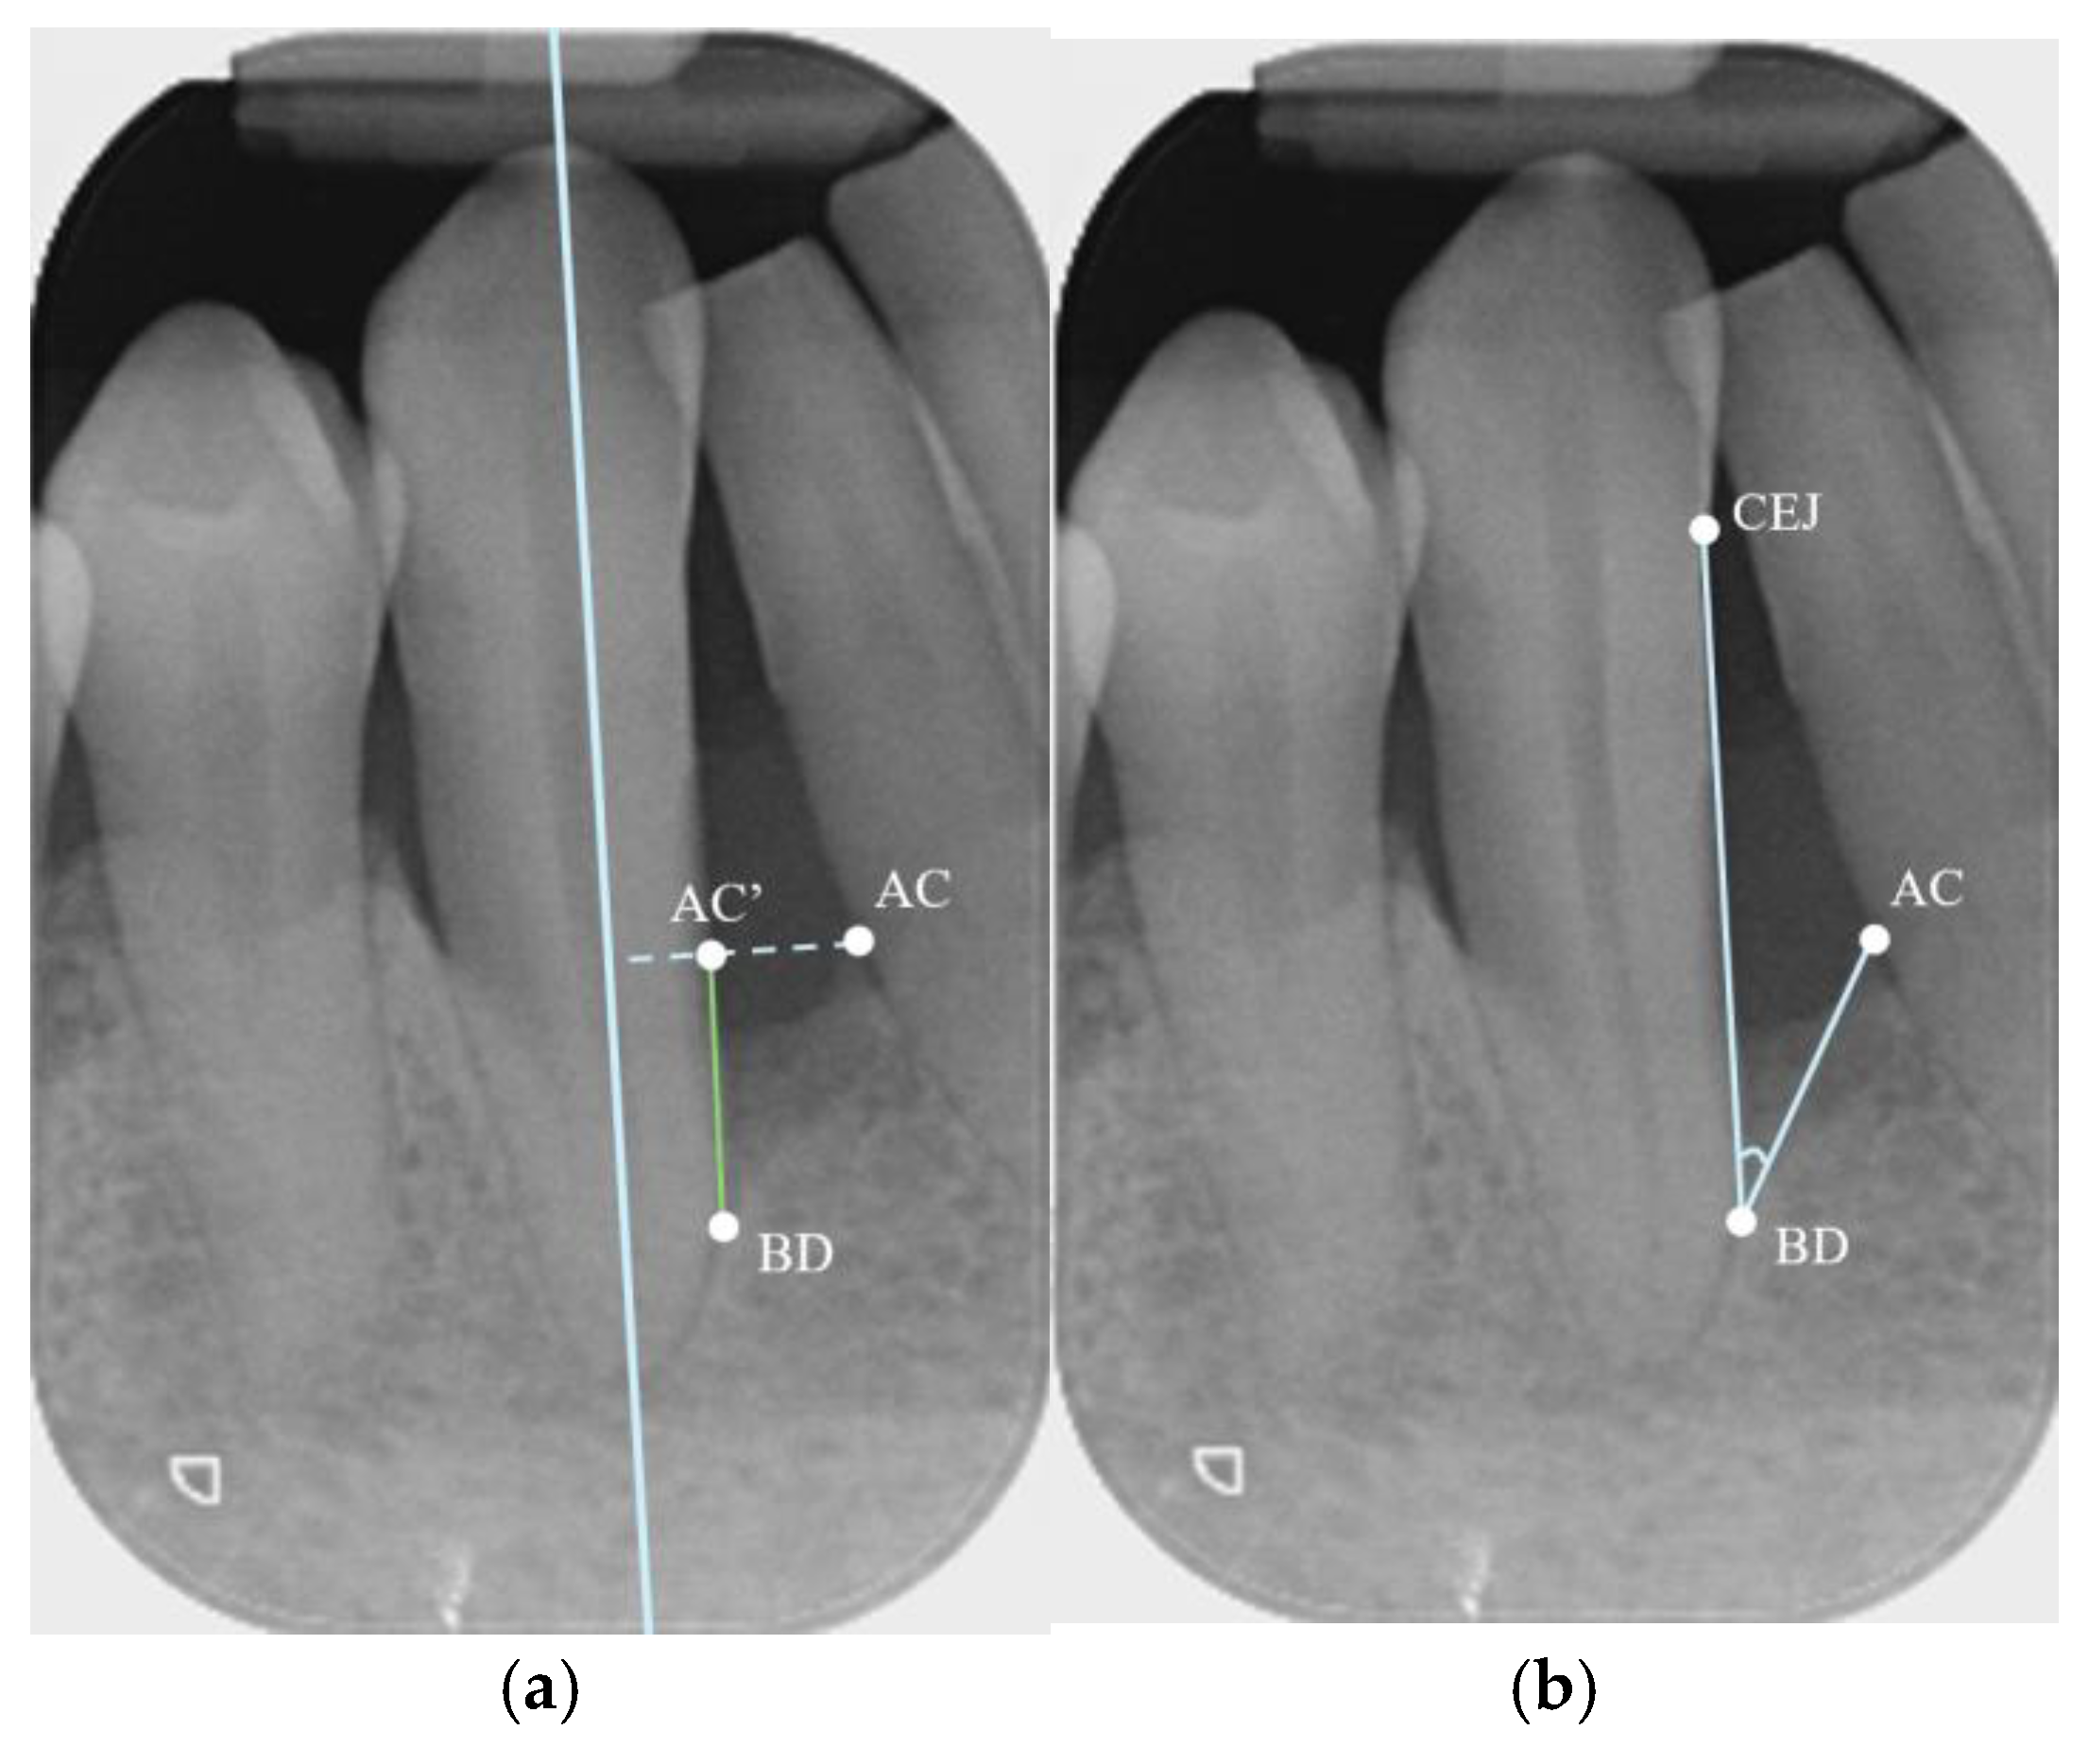

- Parallel Periapical Radiographs (PAs)

- CBCT